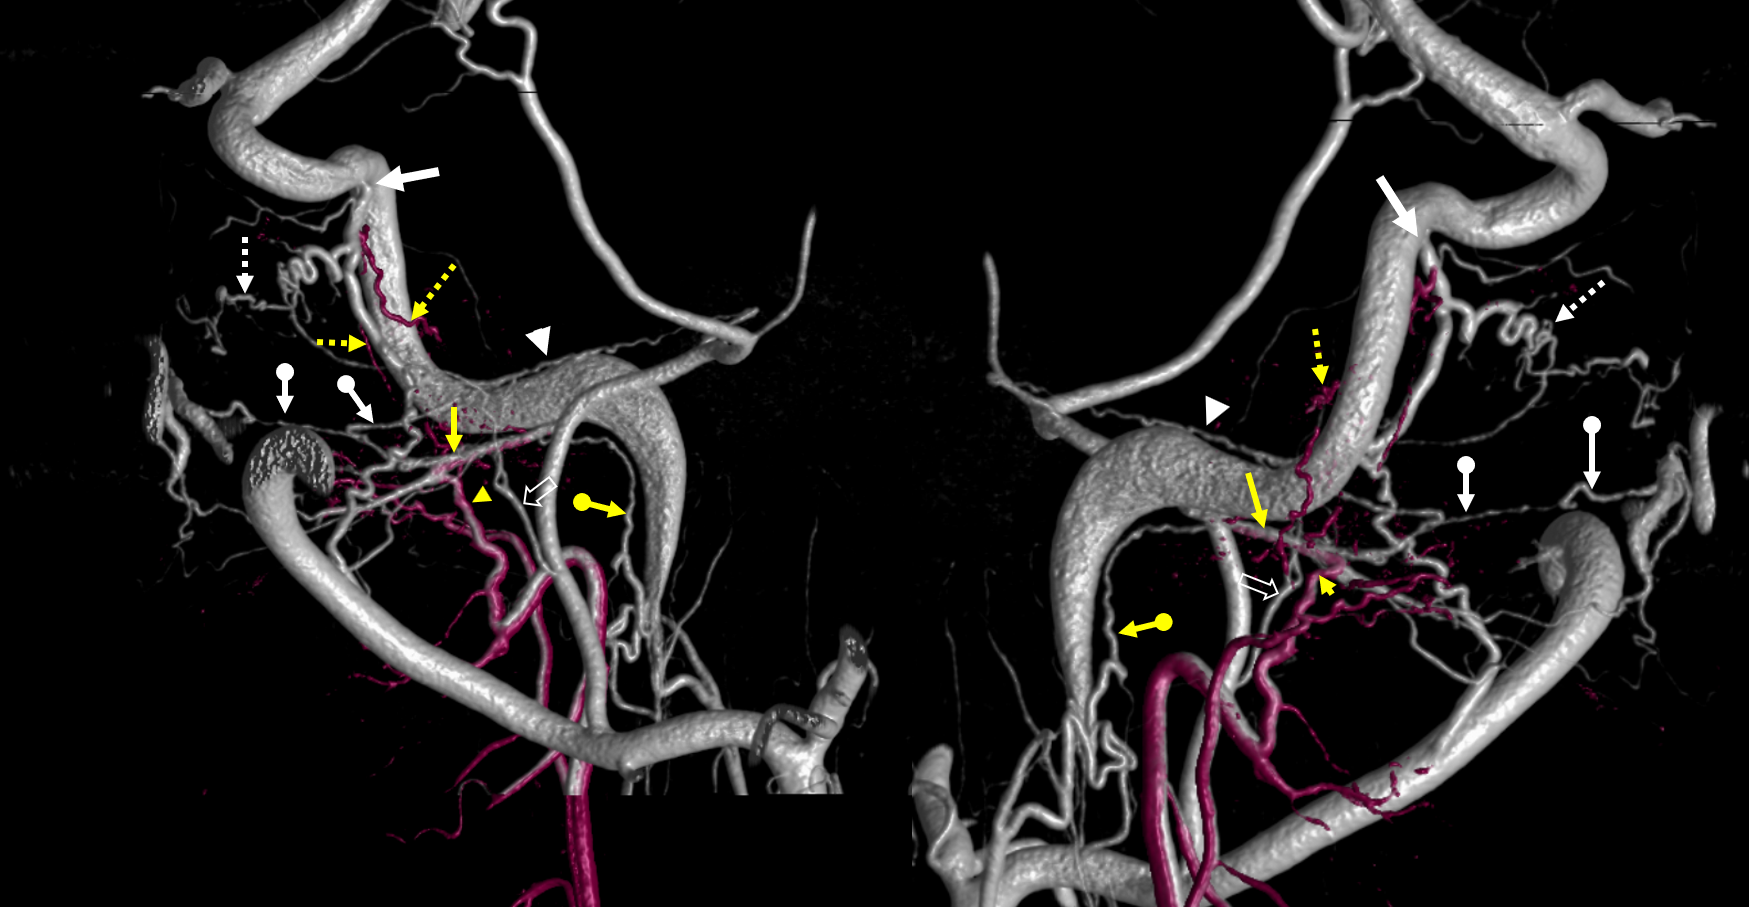

Jugular branch and extensive anastomoses in setting of Moya-Moya and synangioses.

Patient with bilateral Moya-Moya, post bilateral dural synangiosis and burr hole (see Intracranial Collateral Pathways for the remainder of this case). Stereo image pair on top, with dural/ arterial vasculature in white, and venous outflow in black, outlining an arterial arcade which runs within the dural sheath of the transverse/sigmoid sinuses, partly made up by the jugular branch of the neuromeningeal trunk. Anastomoses with middle meningeal and occiptal branches are clearly demonstarated. These arteries frequently participate in supply of sigmoid sinus dural fistulas.

•Red – ascending pharyngeal artery, neuromeningeal trunk

•Pink – ascending pharyngeal artery, jugular branch

•Blue – middle meningeal artery, basal tentorial branch

•Purple – middle meningeal artery, petrosquamosal branch

•White – anastomotic connections between basal tentorial and petrosquamosal branches

•Green –mastoid branch, occipital artery